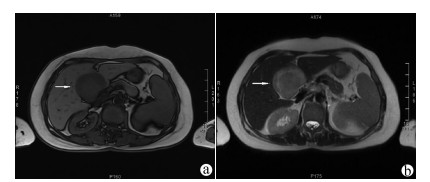

Guideline for ultrasonic diagnosis of liver diseases

Chinese Society of Ultrasound in Medicine, Oncology Intervention Committee of Chinese Research Hospital Society, National Health Commission Capacity Building and Continuing Education Expert Committee on Ultrasonic Diagnosis

2021, 37(8): 1770-1785. DOI: 10.3969/j.issn.1001-5256.2021.08.007

Abstract(3025) HTML (6526) PDF (9311KB)(794)

Abstract:

Ultrasound is a non-invasive, real-time, inexpensive, radiation-free and easily repeatable method, usually used for liver imaging. In recent years, new ultrasound examination techniques for liver diseases such as contrast-enhanced ultrasound and elastography have been rapidly developed, which can effectively identify intrahepatic space-occupying lesions, assess the degree of liver fibrosis and portal hypertension, and monitor the effects of treatment. Therefore, these technologies play an important diagnostic role in clinical liver diseases and have therapeutic interventional value. This guideline classifies the instrument set-up, patient preparation, and physician examination methods through multimodal ultrasound examinations (gray-scale ultrasound, color Doppler ultrasound, contrast-enhanced ultrasound, elastic ultrasound) for liver diseases. In addition, liver diseases multimodal ultrasound technology diagnostic criteria for diffuse hepatic lesions (inflammatory lesions, fibrosis, and sclerosis), multiple space-occupying lesions, and interventional procedures have been defined and standardized. Concurrently, we also recommend the ultrasound monitoring time interval and diagnostic report writing standard for liver diseases.